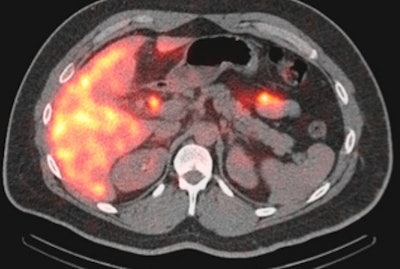

SPECT/CT can be a valuable resource for diagnosing gastrointestinal and genitourinary bleeding in the emergency room setting, and it does so in a reasonable amount of additional time, according to a study from Stony Brook University.

Researchers found that SPECT/CT correctly identified the cause of bleeding in 22 (96%) of 23 patients who had inconclusive results from standard dynamic imaging studies. The hybrid modality was also precise in locating abnormalities and led to more accurate interventions for patients.

Traditional nuclear medicine gastrointestinal and genitourinary studies to detect bleeding use dynamic and static or planar images to come to a diagnosis. However, these types of imaging modalities are often not sufficient to arrive at a final conclusion. By comparison, SPECT/CT is better at localizing the source of problem, while CT provides better definition of anatomy and higher spatial resolution.

SPECT/CT was performed at the end of dynamic imaging and deemed helpful in 22 (96%) of the 23 cases, allowing clinicians to identify the regional anatomy as the source of gastrointestinal bleeding in all six cases.

Of those six patients, four diagnoses of bleeding were in the large bowel and two were in the small bowel. One patient (17%) had both a small bowel and a peritoneal bleed, which was confirmed by surgery. Three patients (50%) had multiple prior studies performed, which were inconclusive before SPECT/CT.

SPECT/CT successfully localized nine (64%) biliary leaks among the 14 hepatobiliary studies. In addition, the modality confirmed three cases (21%) of atresia and excluded cholecystitis in two patients (14%) by identifying the gallbladder as the source of the bleeding.

Among the other patients, SPECT/CT was able to identify the precise location of a urinary leak in a renal transplant patient, but it was inconclusive for the lone Meckel's diverticulum study.